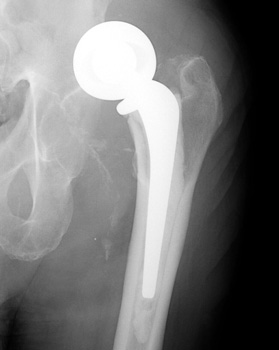

Dislocated total hip replacement